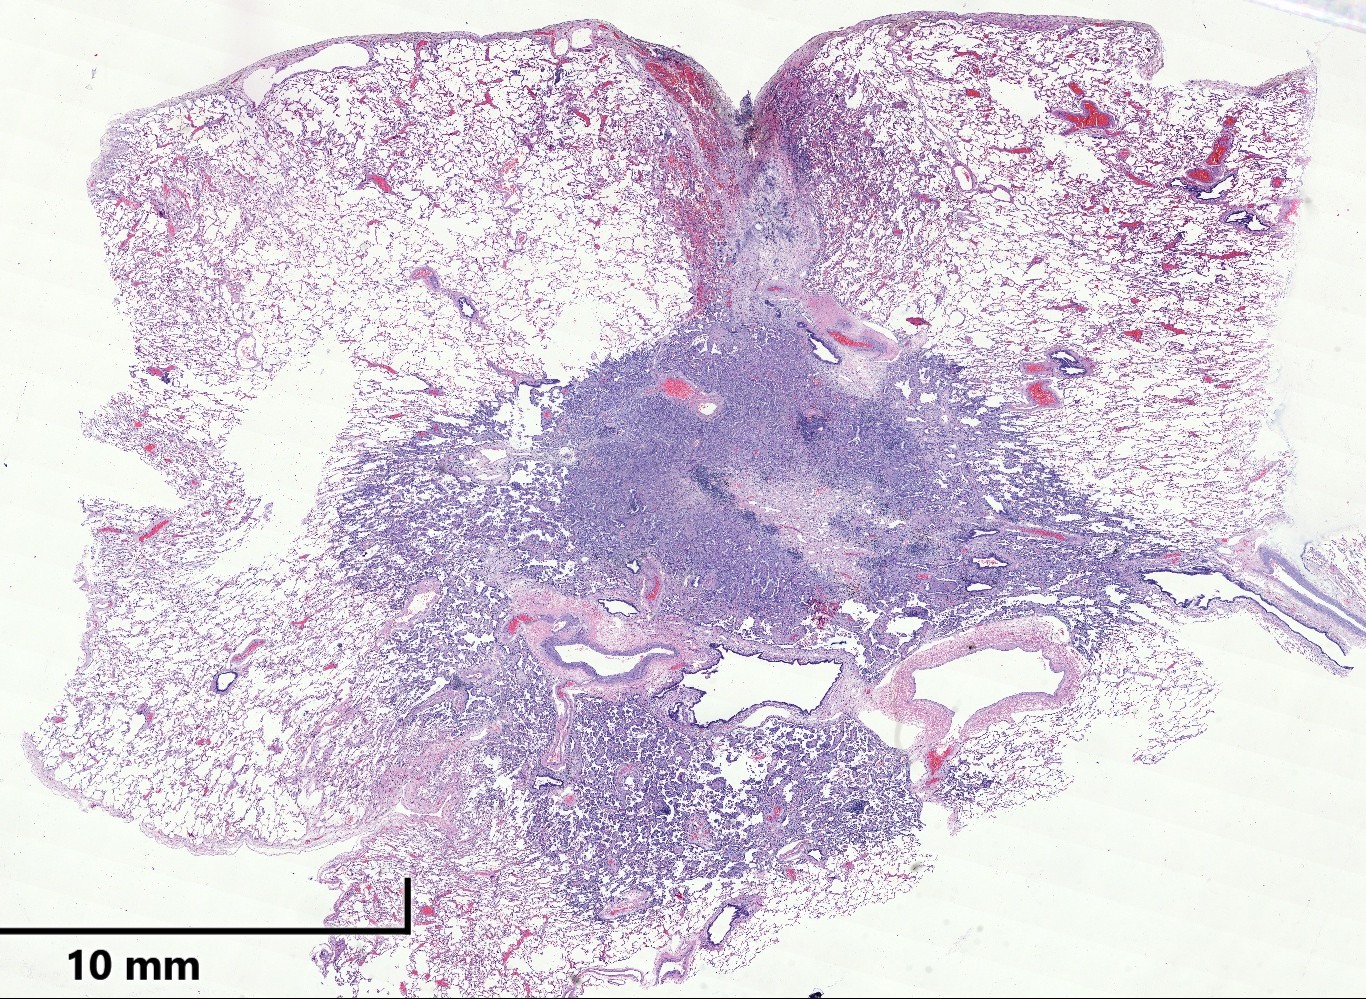

Patología Molecular

El diagnóstico sobre muestras de tejidos y líquidos corporales en plena era de la medicina del futuro, está basado en la integración de técnicas y conocimientos diferentes.

Hoy más que nunca es importante integrar una buena historia clínica con un correcto estudio de imagen y una buena morfología que además puede estar apoyada con proceso especiales complementarios relacionados con la Inmunología, Biología Molecular y Citogenética, generando así un estudio integral conocido como Patología Molecular.